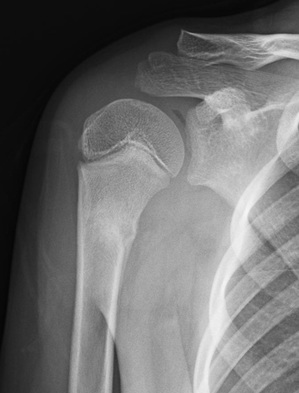

受傷時のレントゲンです。矢印で刺した部分で上腕骨がぐにゃっと曲がっています。

痛みが強かったので、右上肢を「てつり」で固定しました。

1週間後には痛みがほとんどなくなったので、「てつり」を外し、自分の力で右腕をあげないように指導しました。(自動挙上禁止)

受傷後2週間でほとんど痛みがなくなり、レントゲン上も仮骨がみえたので、痛くない範囲で右腕を動かしていいと指導しました。(自動挙上許可)

受傷4週間後には、痛みは完全に良くなり、肩の動きの制限もなくなったので、転ばないように注意すればサッカーもしていいと許可して、治療を終了しました。

このように、こどもの骨折はバキッと折れずにぐにゃっと曲がります。こどもの場合4週間で治りますが、大人が同じ場所を骨折した場合、8週間以上かかります。